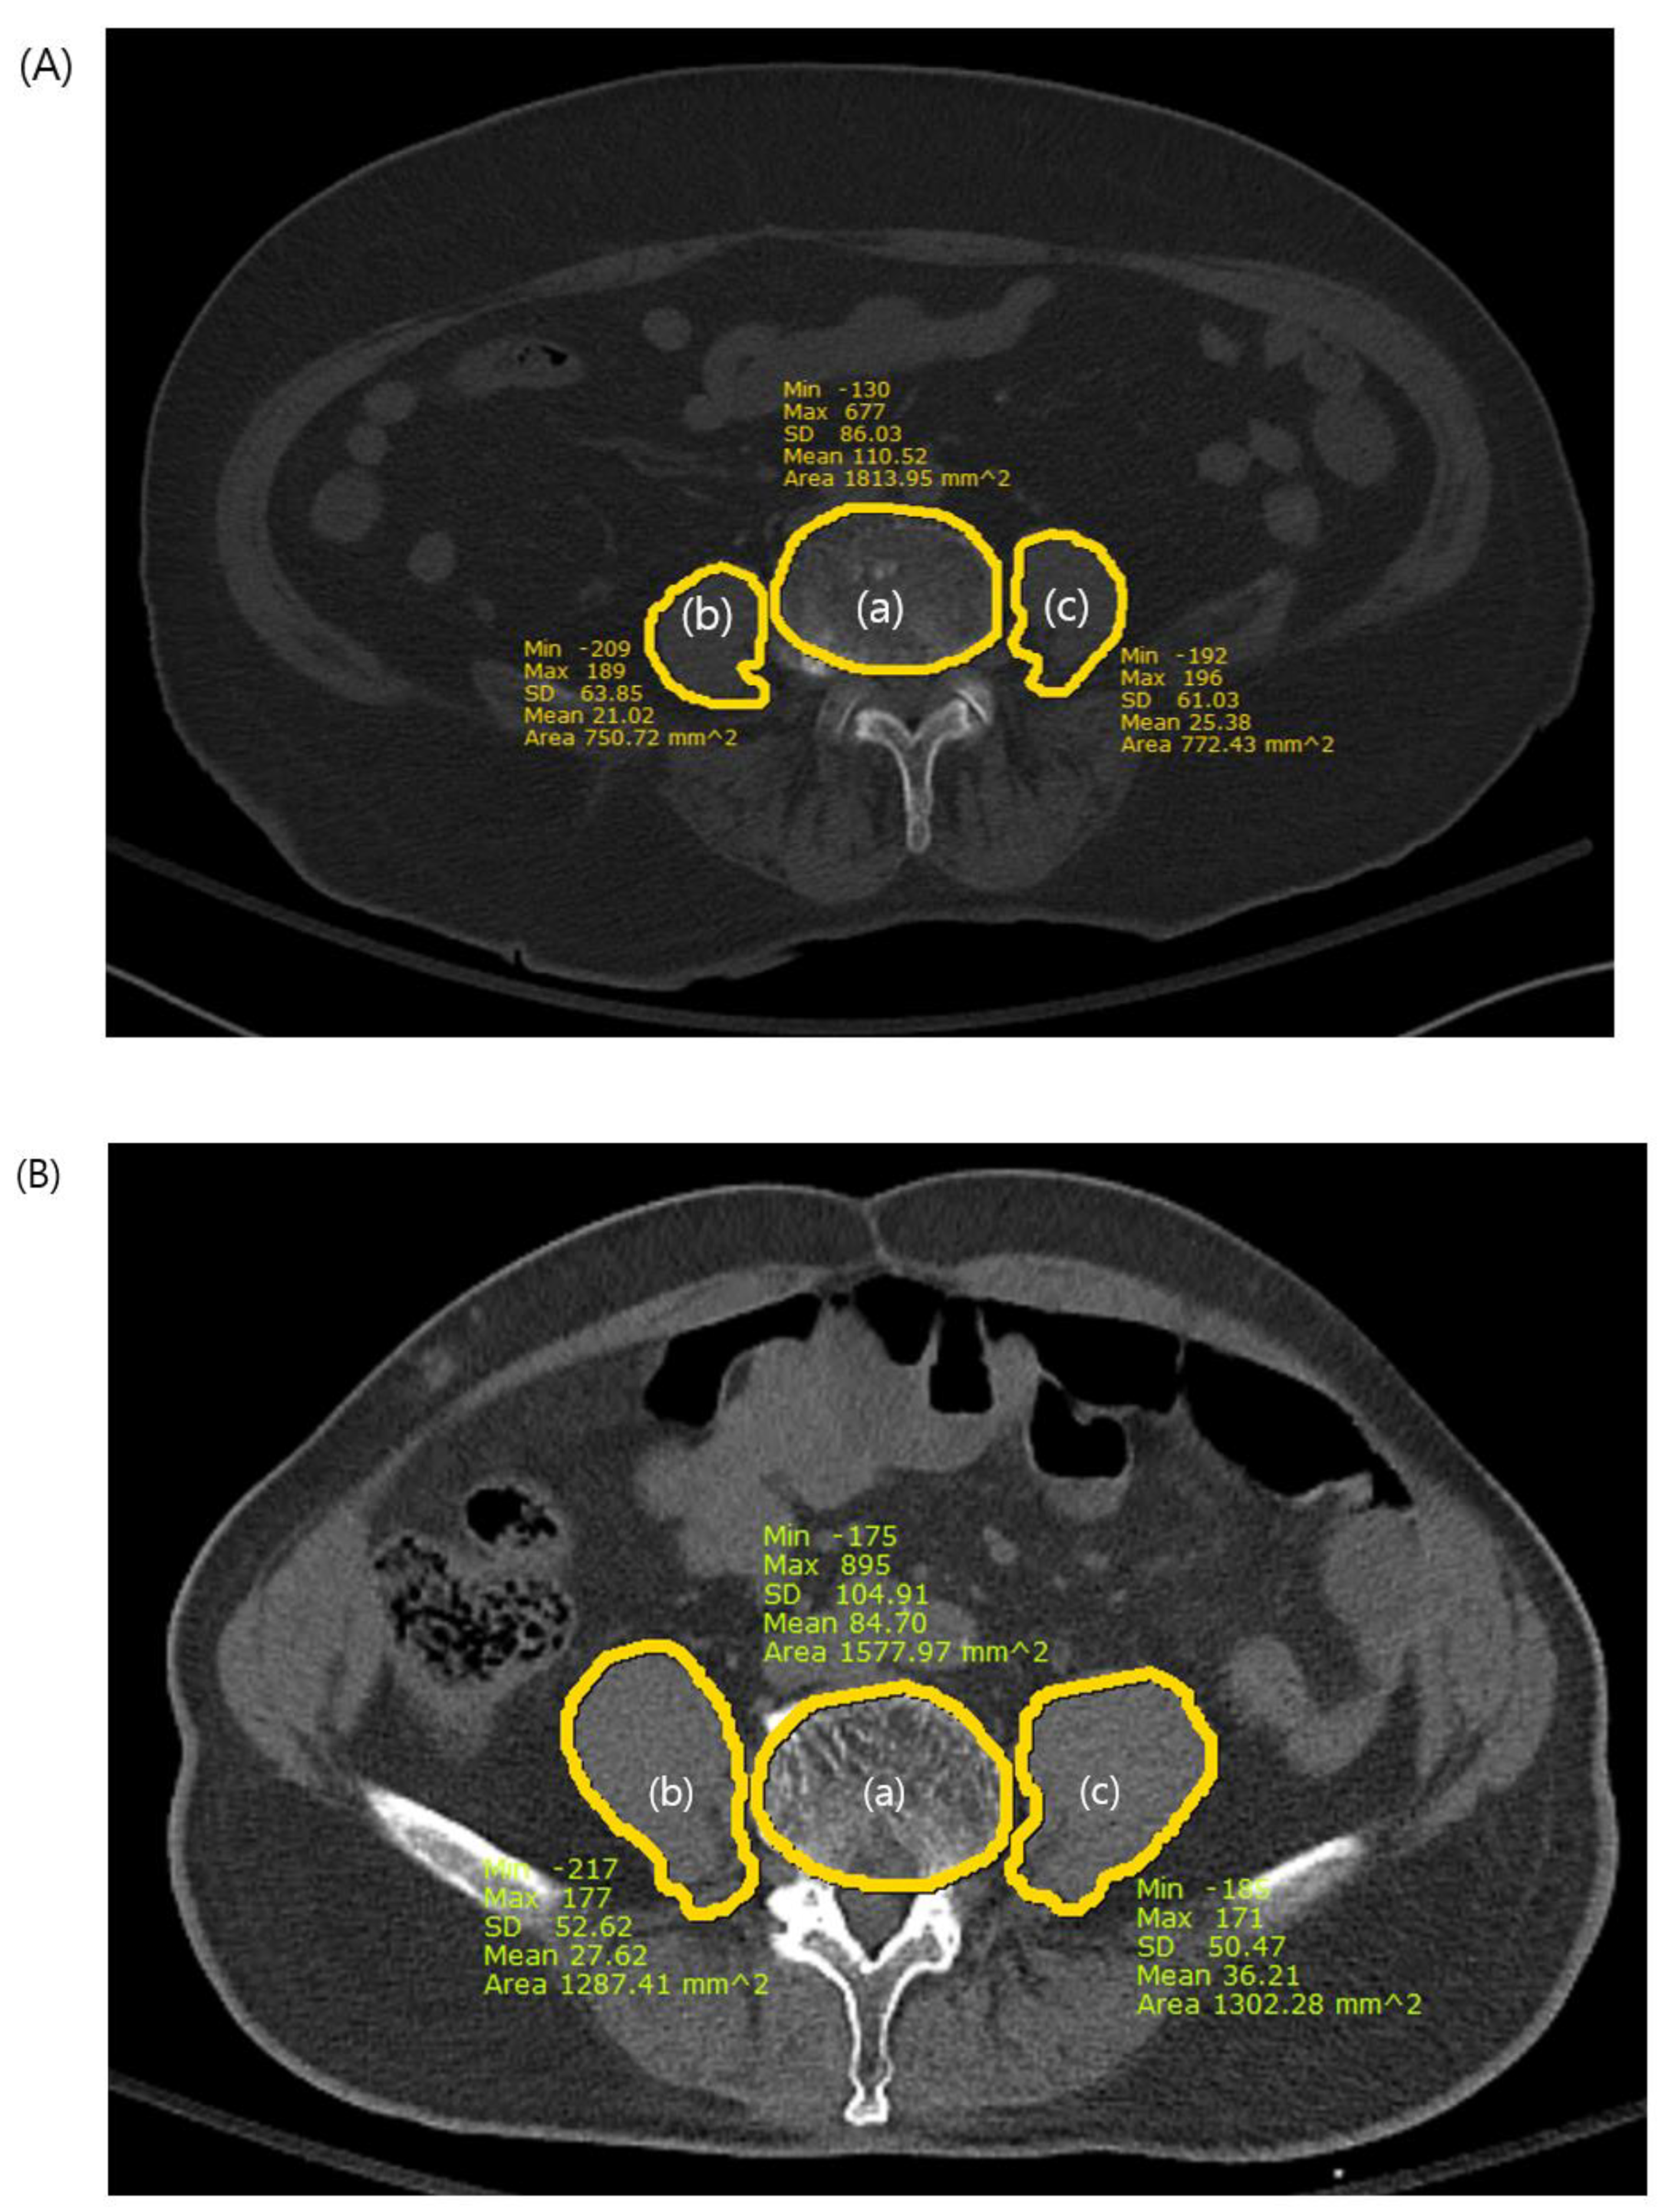

We measured the psoas-lumbar vertebral index (PLVI) to evaluate central sarcopenia from axial sections of preoperative CT images using measurements from the picture archiving and communication system (PACS). The PLVI was established following the criteria established in previous studies [11,12,13] and was calculated as the ratio of the average of the areas of both the right and left psoas muscles at the level of the inferior endplate of the fourth lumbar vertebra to the area of the fourth lumbar vertebra (Figure 2). Sarcopenia was defined as a PLVI within the lowest 25% for each sex [7,9,10], and patients were categorized into sarcopenic and nonsarcopenic groups for analysis.

Figure 2.

The psoas-lumbar vertebral index (PLVI) measurement. (a) L4 vertebral body area, (b) right psoas area, (c) left psoas area. PLVI = [(b + c)/2]/a (A): PLVI of the sarcopenic patient on computed tomography. The PLVI= 0.41. (B): PLVI of the nonsarcopenic patient on computed tomography. The PLVI = 0.84.